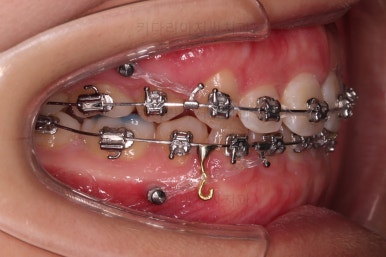

원하시는 목표량은 이 뽑은 자리로 앞니를 다 넣어도 안될 듯 하여 추가로 사랑니 발치를 하고 미니스크류를 이용해서 더 넣어보기로 했어요.

위아래 좌우 모두 사랑니도 발치를 하고 네 군데 모두 미니스크류를 하여 최대한 당겨보기로 하였습니다.

이 쯤 되면 좋은 듯 한데, 그래도 아쉬운가 봅니다.

그래서 사직동교정치과 더 넣어보기로 했어요.

아무래도 입술이 두툼하신터라 표시가 그렇게 많이 안나는 점이 아쉬웠나 봐요.

그래서 일반적인 발치치료보다 치료기간이 늘어났어요.